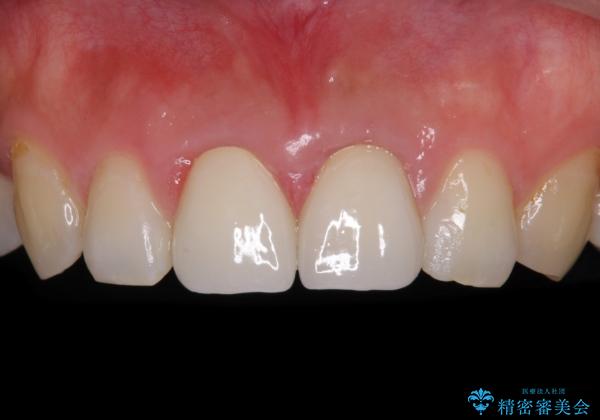

変色した前歯のクラウン オールセラミッククラウンにより審美歯科治療

- 前歯のクラウンが着色により不自然な色となっていることを気にして来院された患者様です。

クラウンと歯の縁も合っておらず、汚れが溜まりやすい環境であったため、前歯2歯のクラウンをオールセラミッククラウンにて再補綴することとしました。

下顎前歯の部分矯正に半年ほどかかってしまい、少し期間は長いものとなりましたが、上下ともに前歯がきれいに整い、患者様には大変満足していただきました。